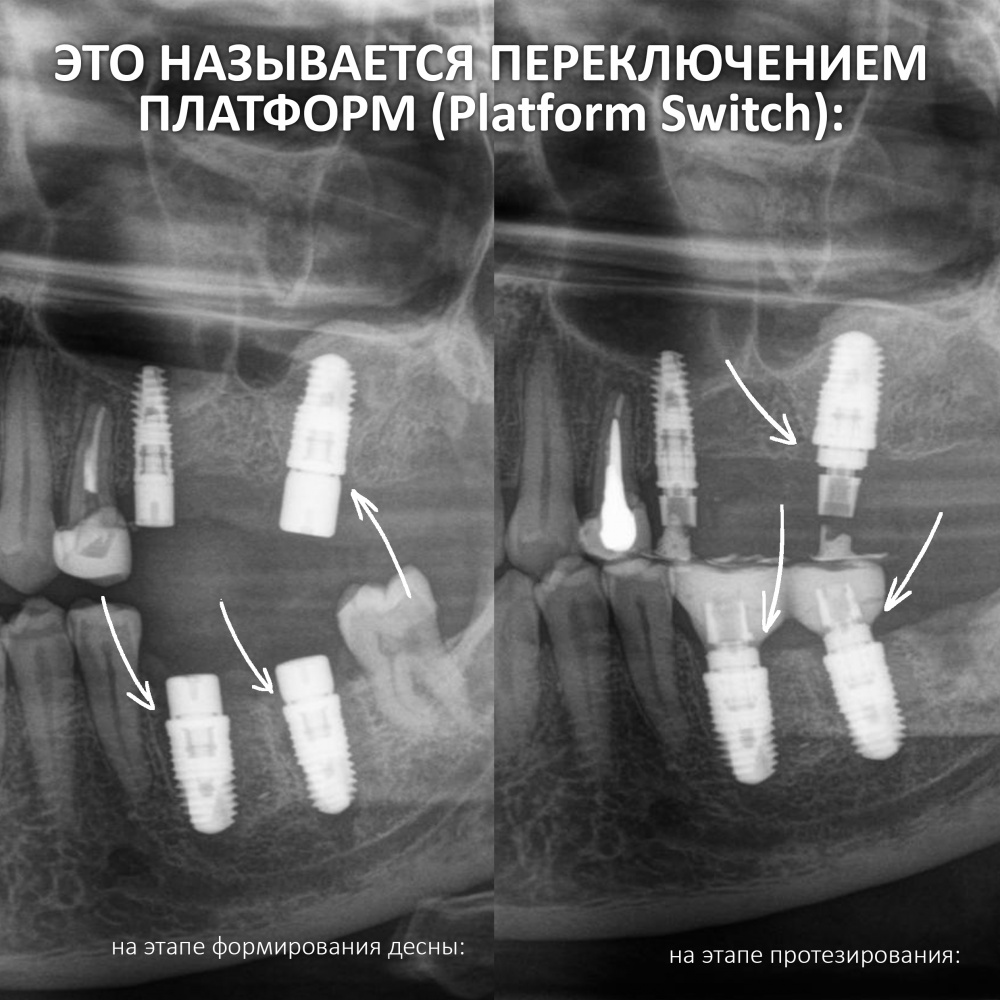

Условие 4. Возможность фиксации платформы имплантата на границе роста.

Граница роста — гипотетическая поверхность, разделяющая васкуляризированный жизнеспособный графт от нежизнеспособного и подлежащего резорбции. Граница роста никогда не совпадает с созданным в ходе остеопластики контуром регенерата вследствие сопровождающих регенерацию патофизиологических процессов, популярно называемых «усадкой» или резорбцией графта.

Точно определить пространственное положение границы роста не представляется возможным, поскольку она зависит от множества факторов: начиная от метода остеопластики и используемых биоматериалов, заканчивая биотипом костной ткани, состоянием микроциркуляторного русла и т. д. Все это имеет серьезное значение при планировании имплантации с одновременной остеопластикой.

Например, мы проводим горизонтальную остеопластику, увеличиваем толщину альвеолярного гребня и одновременно устанавливаем имплантаты. В процессе интеграции графта происходит его «усадка» на 1-2 мм, но даже в этом случае платформа имплантата остается в правильном положении относительно поверхности костной ткани.

В процессе регенерации после вертикальной остеопластики (любым из методов) мы стабильно теряем около 1-2 мм запланированной высоты, а иногда и больше — опять же, это связано с особенностями васкуляризации и заселения графта живыми клетками. В таком случае точная установка имплантатов вряд ли возможна, поскольку утрата миллиметров в пришеечной области серьезно скажется на конечном результате лечения.

В подобных ситуациях намного разумнее дождаться окончательной интеграции графта, добиться внятной фиксации границы роста — и уже потом, с её учетом рассматривать позиционирование и установку имплантатов.

Иными словами, непредсказуемость положения границы роста существенно ограничивает нас в возможности установки имплантатов одновременно с остеопластикой — и особенно часто это происходит при вертикальном наращивании костной ткани.

Чуть выше в этой статье я упоминал о т. н. «границе роста», гипотетической поверхности, разделяющий жизнеспособный и атрофированный графт. Предсказать положение границы роста не представляется возможным, но при этом критически важно, чтобы платформа имплантата не оказалась за её пределами. Так вот, в случае с горизонтальной остеопластикой граница роста более-менее устойчива по высоте, поскольку «усадка графта» происходит, в основном, в горизонтальном направлении:

Поэтому операции горизонтальной остеопластики хорошо предсказуемы, а позиционирование платформы имплантата на границе роста не представляет каких-либо сложностей.

Несколько иная ситуация с вертикальной остеопластикой. Особо это касается столь любимого многими метода направленной костной регенерации (НКР) с резорбируемым каркасом — при проведении подобных операций «усадка» графта может достигать 15-20%. Поэтому предсказать итоговое положение границы роста сложно, практически невозможно. Следовательно, таким же невозможным представляется позиционирование имплантатов по высоте — риски того, что платформа окажется выше границы роста, весьма высоки.

Компромиссным (т. е. неидеальным) решением в таких случаях является использование субкрестальных имплантатов, у которых положение платформы по вертикальной оси не является слишком уж критическим. Например, используемые нами имплантаты Anlylos C/X можно заглубить в костную ткань на 4,5 мм (это длина трансгингивальной части самого длинного абатмента). Таким образом, «утопив» субкрестальные имплантаты в графт на 4 мм мы не потеряем в качестве протезирования даже в случае, если «усадка» графта составит 2-3 мм — платформа имплантата всё равно останется в нужном положении.